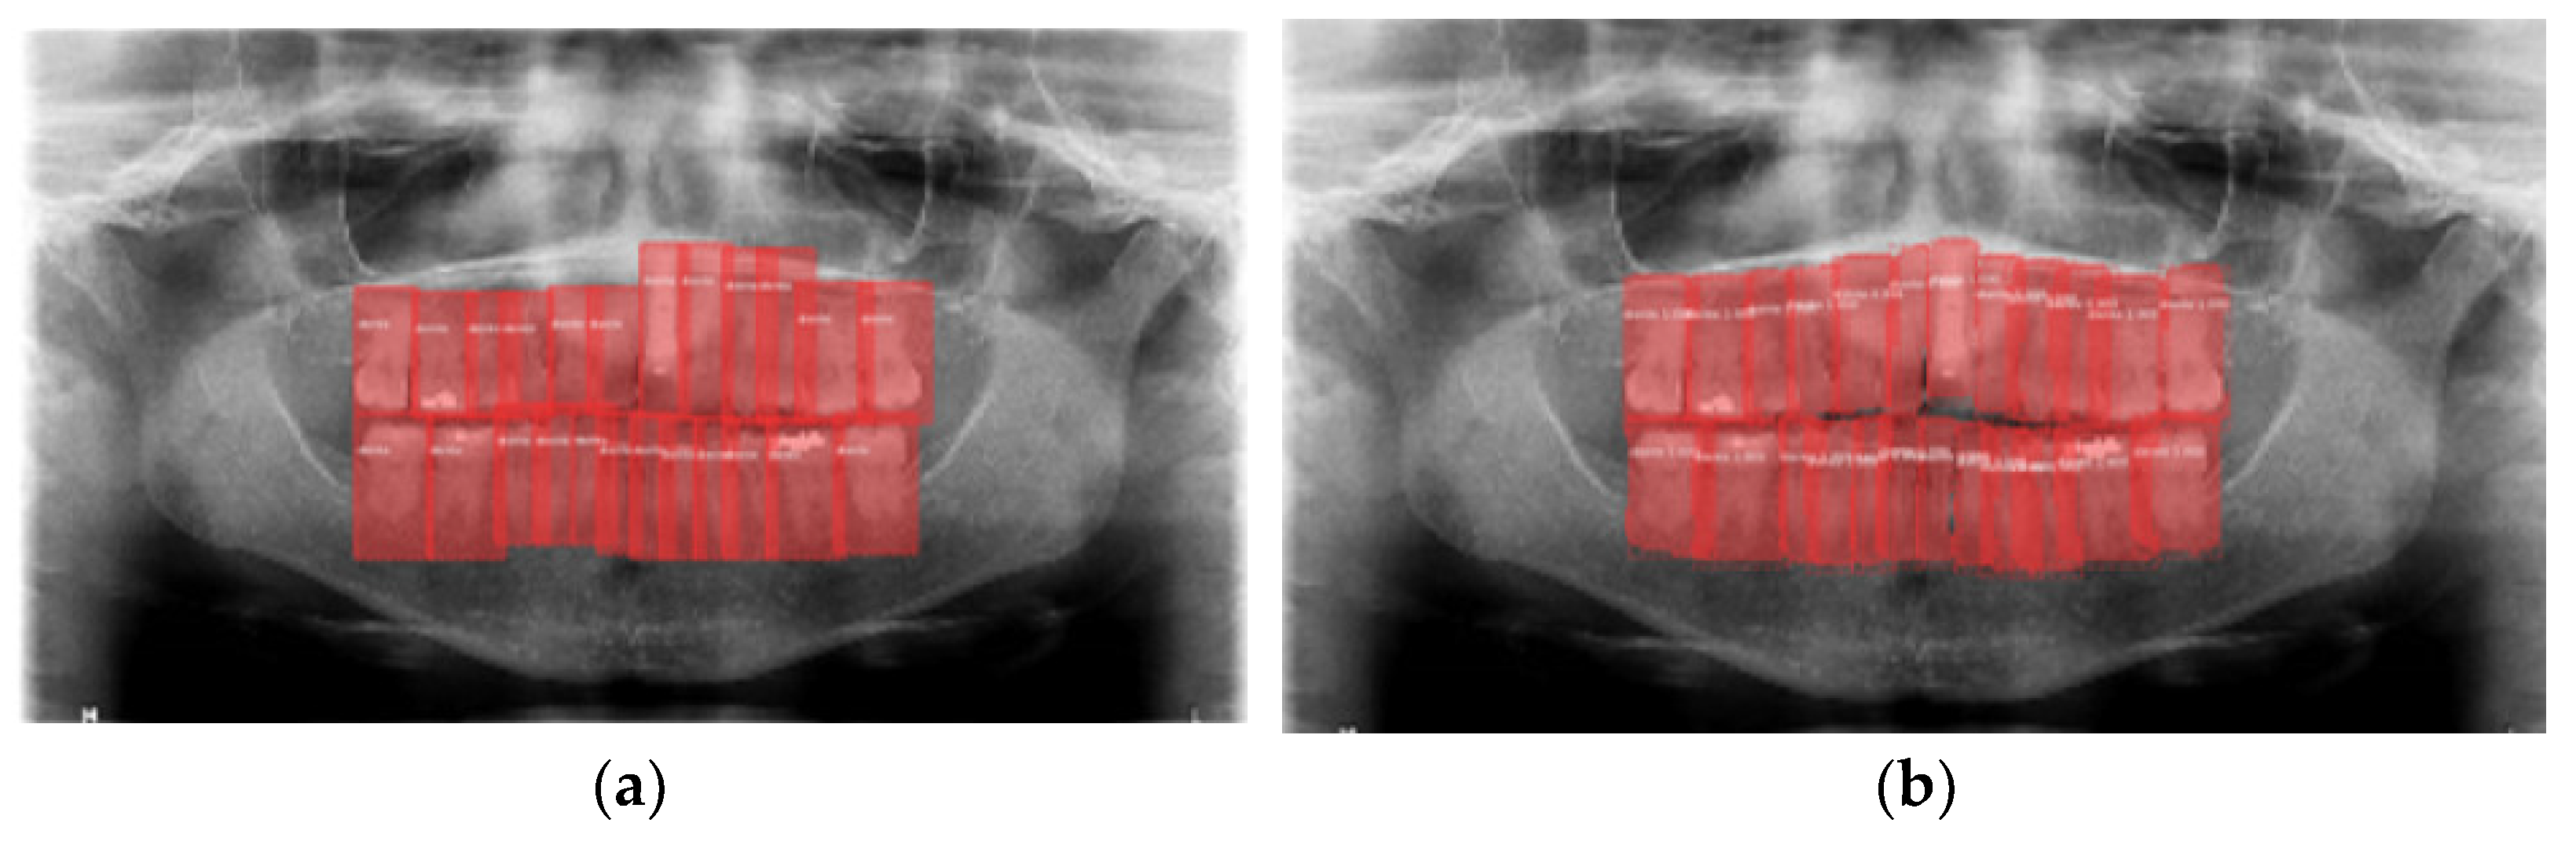

3.2. Teeth Detection Results

3.4. Model Execution Examples

4. Discussion